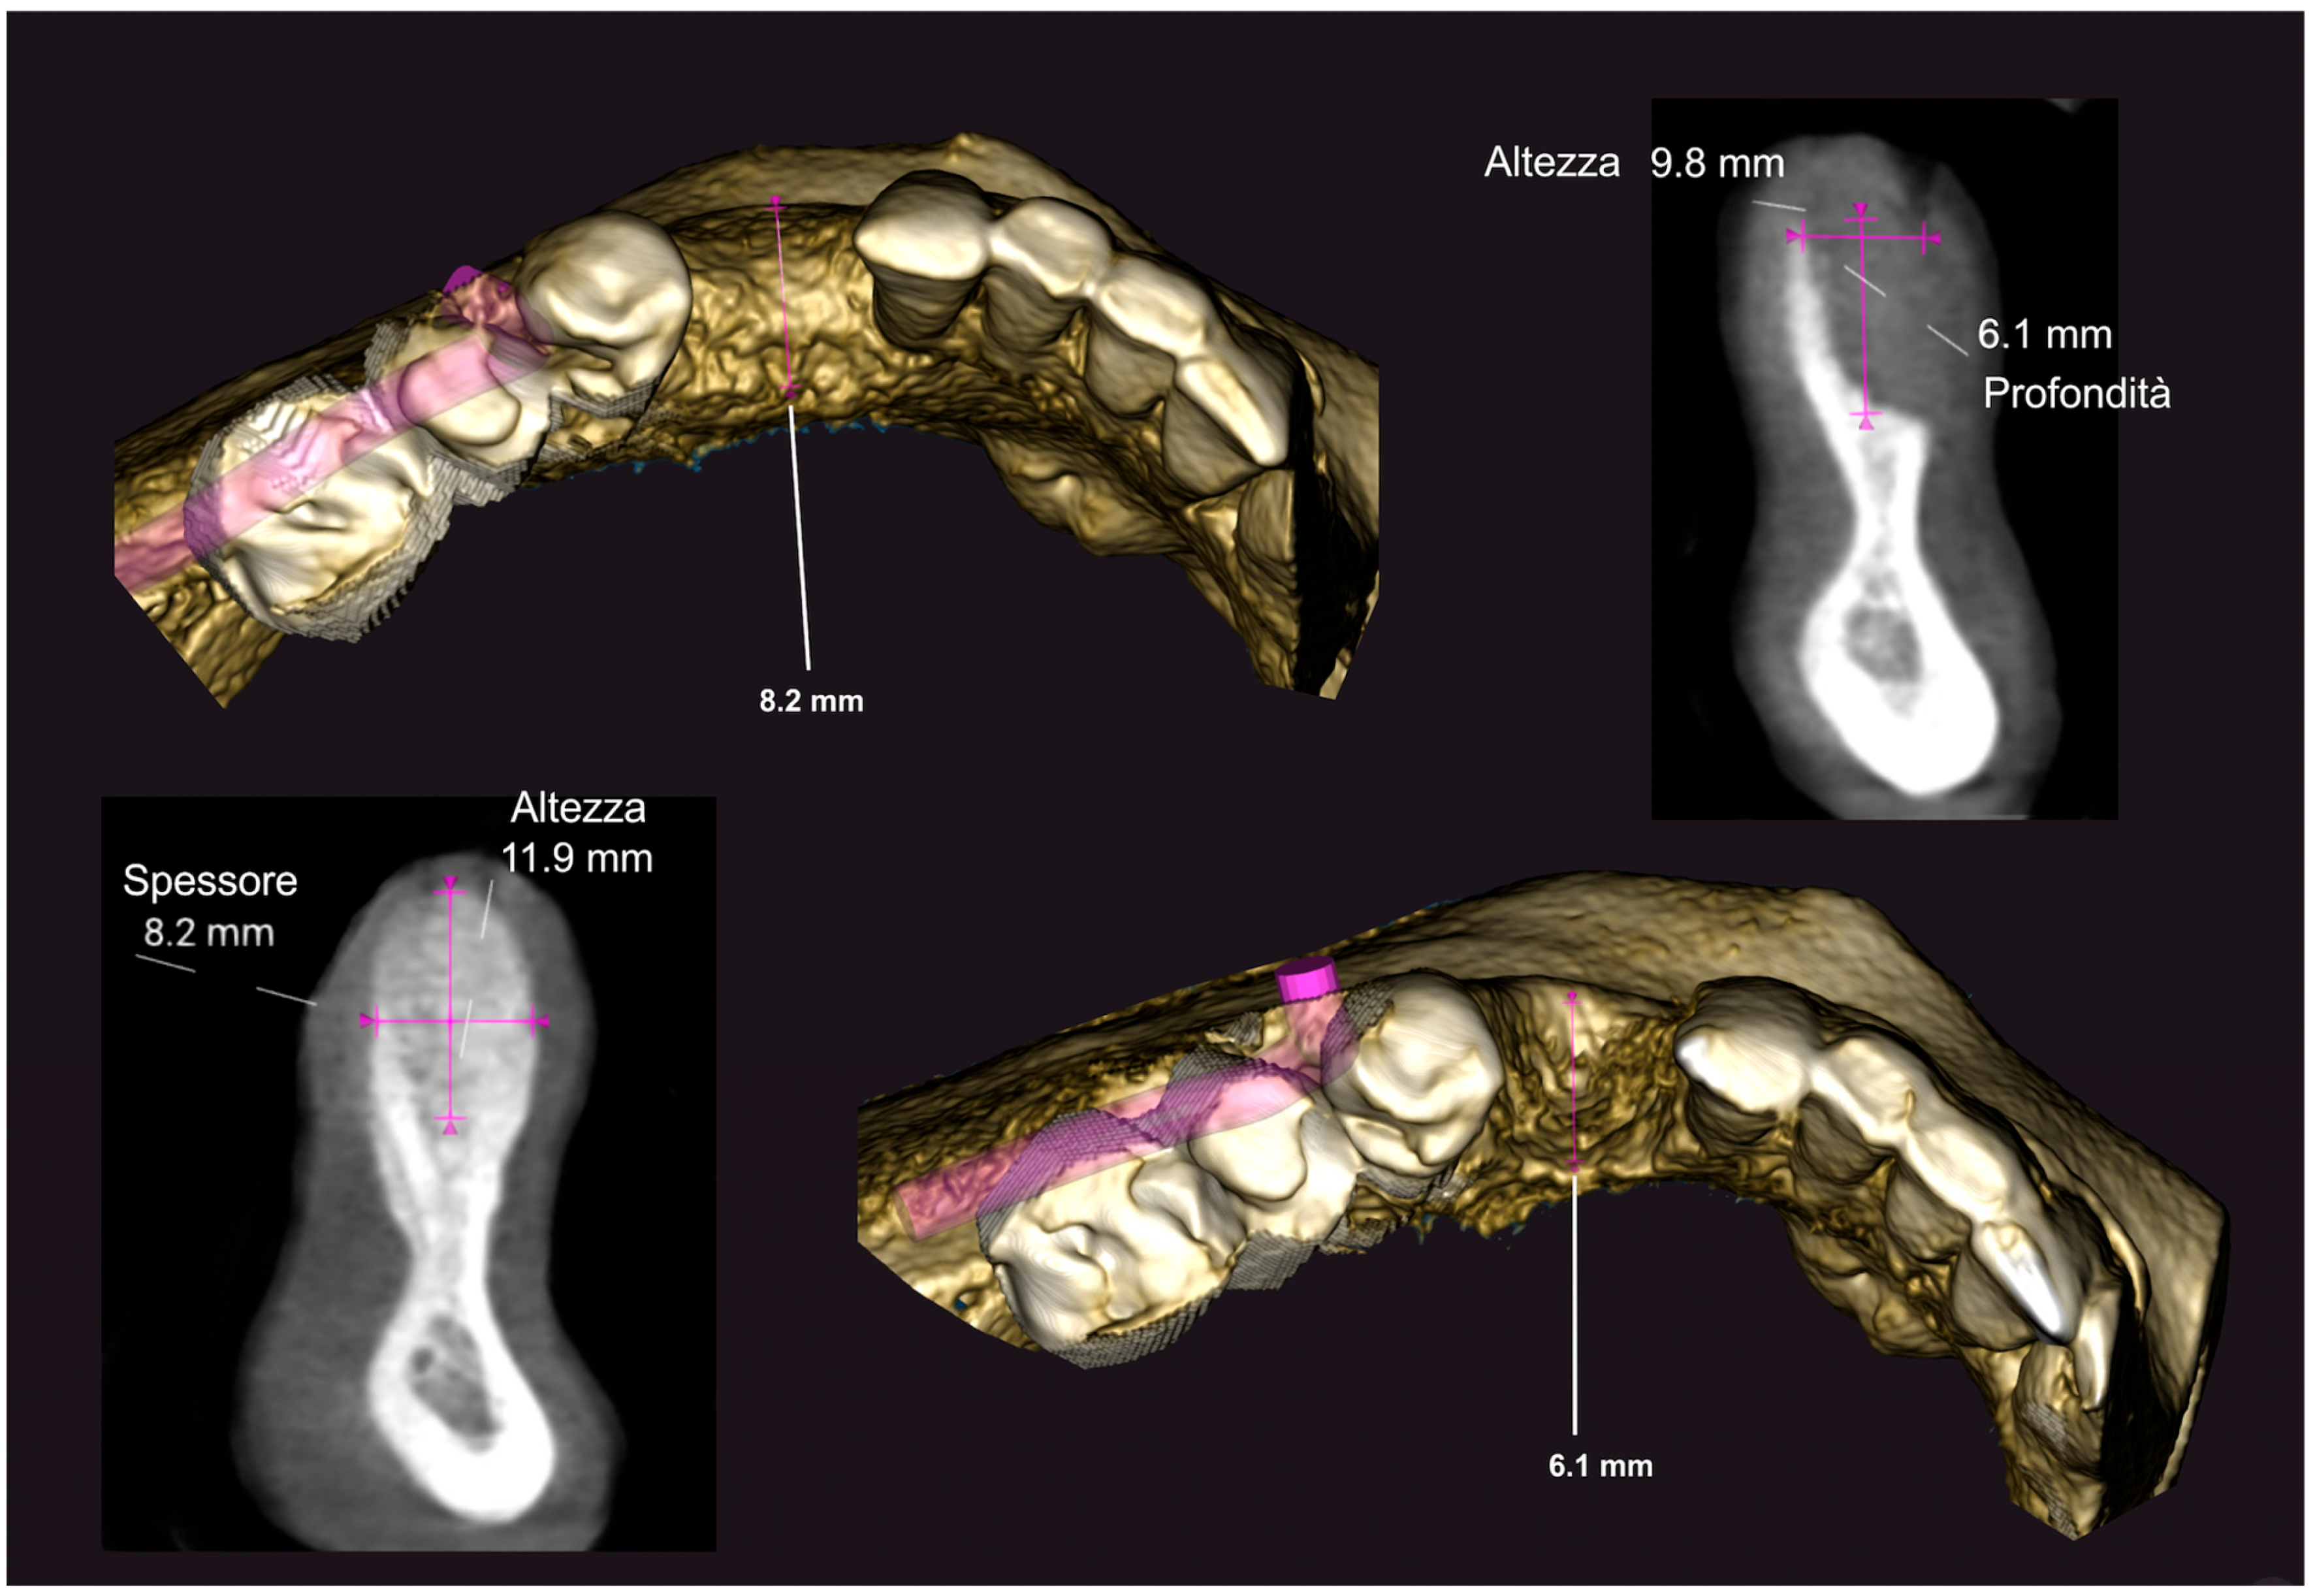

4. Results

Five sites in five patients of ages 26 to 59 with severe ridge deformities were treated with segmented bone lamina. In Table 1 we report the position and extent of the defects. All lesions were measured by CBCT and at surgery with a 15 mm PCP periodontal probe (Figure 17). The thickness of the residual buccal or lingual wall was measured and recorded and as a vertical component the reference point of measurement was the highest bone peak available. After the bone graft and the bone lamina were glued in position the site was re-measured to calculate the augmentation at baseline. Eight months after augmentation the pre-operative CBCT and the follow up CBCT were compared to re-measure the outcome of the procedure (Figure 18). The volumetric changes were evaluated by comparison using Exocad software and on the CBCT on the cross-sections where augmentation was performed (Figure 19 and Figure 20).

In this small sample, four of the residual bone defects had at least one wall of bone available while only one case had both buccal and lingual walls completely missing. In this case the reference point used to assess measurements was the highest bone peak available at the adjacent tooth. The average gain in the horizontal component was 6.18 mm (±1.19 mm), while the average vertical augmentation was 9.70 mm (±2.39 mm).

Figure 18. CBCT Comparison before and after augmentation. In yellow the new volume.

Medicina 61 00683 g018

Figure 19. CBCT comparison, baseline and 8 months after GBR.

Medicina 61 00683 g019

Figure 20. Comparison of CBCT at baseline and 8 months after GBR.

Medicina 61 00683 g020